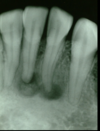

is the following periapical pathology or not?

yes

83

yes - root filled - PDL isnt continuous - lamina dura isnt continuous